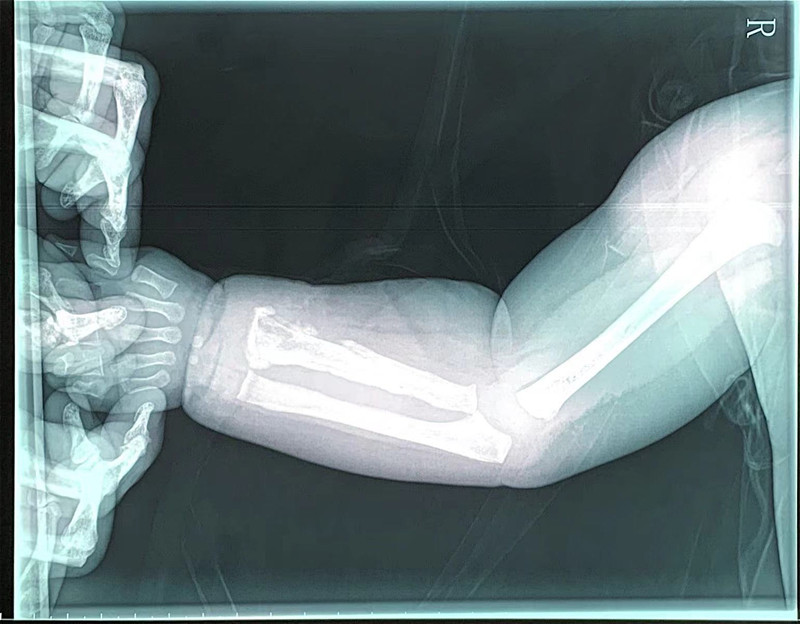

7月13日上午,1岁男宝小宇(化名)住进了啪啪网 骨、泌尿、烧伤科,他不明白为什么自己的胳膊会又疼又肿,更不知道一种叫“急性骨髓炎”的疾病正在侵扰着他。

局部切开,减压、引流

小宇一周前发过烧,后来胳膊肿了。小宇妈妈说,原以为孩子只是普通感冒,打针后烧退了,但胳膊一直不见好转。这种情况,医生怀疑是急性骨髓炎。拍片显示,其桡骨骨质改变,结合核磁检查结果,医生综合分析,明确是急性骨髓炎。由于已错过发病初期48小时最佳治疗期,不能保守治疗,医生建议马上手术。随后,副主任医师高凤奇为小宇手术,局部切开、病灶清除、开窗减压、置管冲洗引流,术后又进行抗感染治疗。2周后,小宇症状改善,无肿痛、无化脓液,基本痊愈。